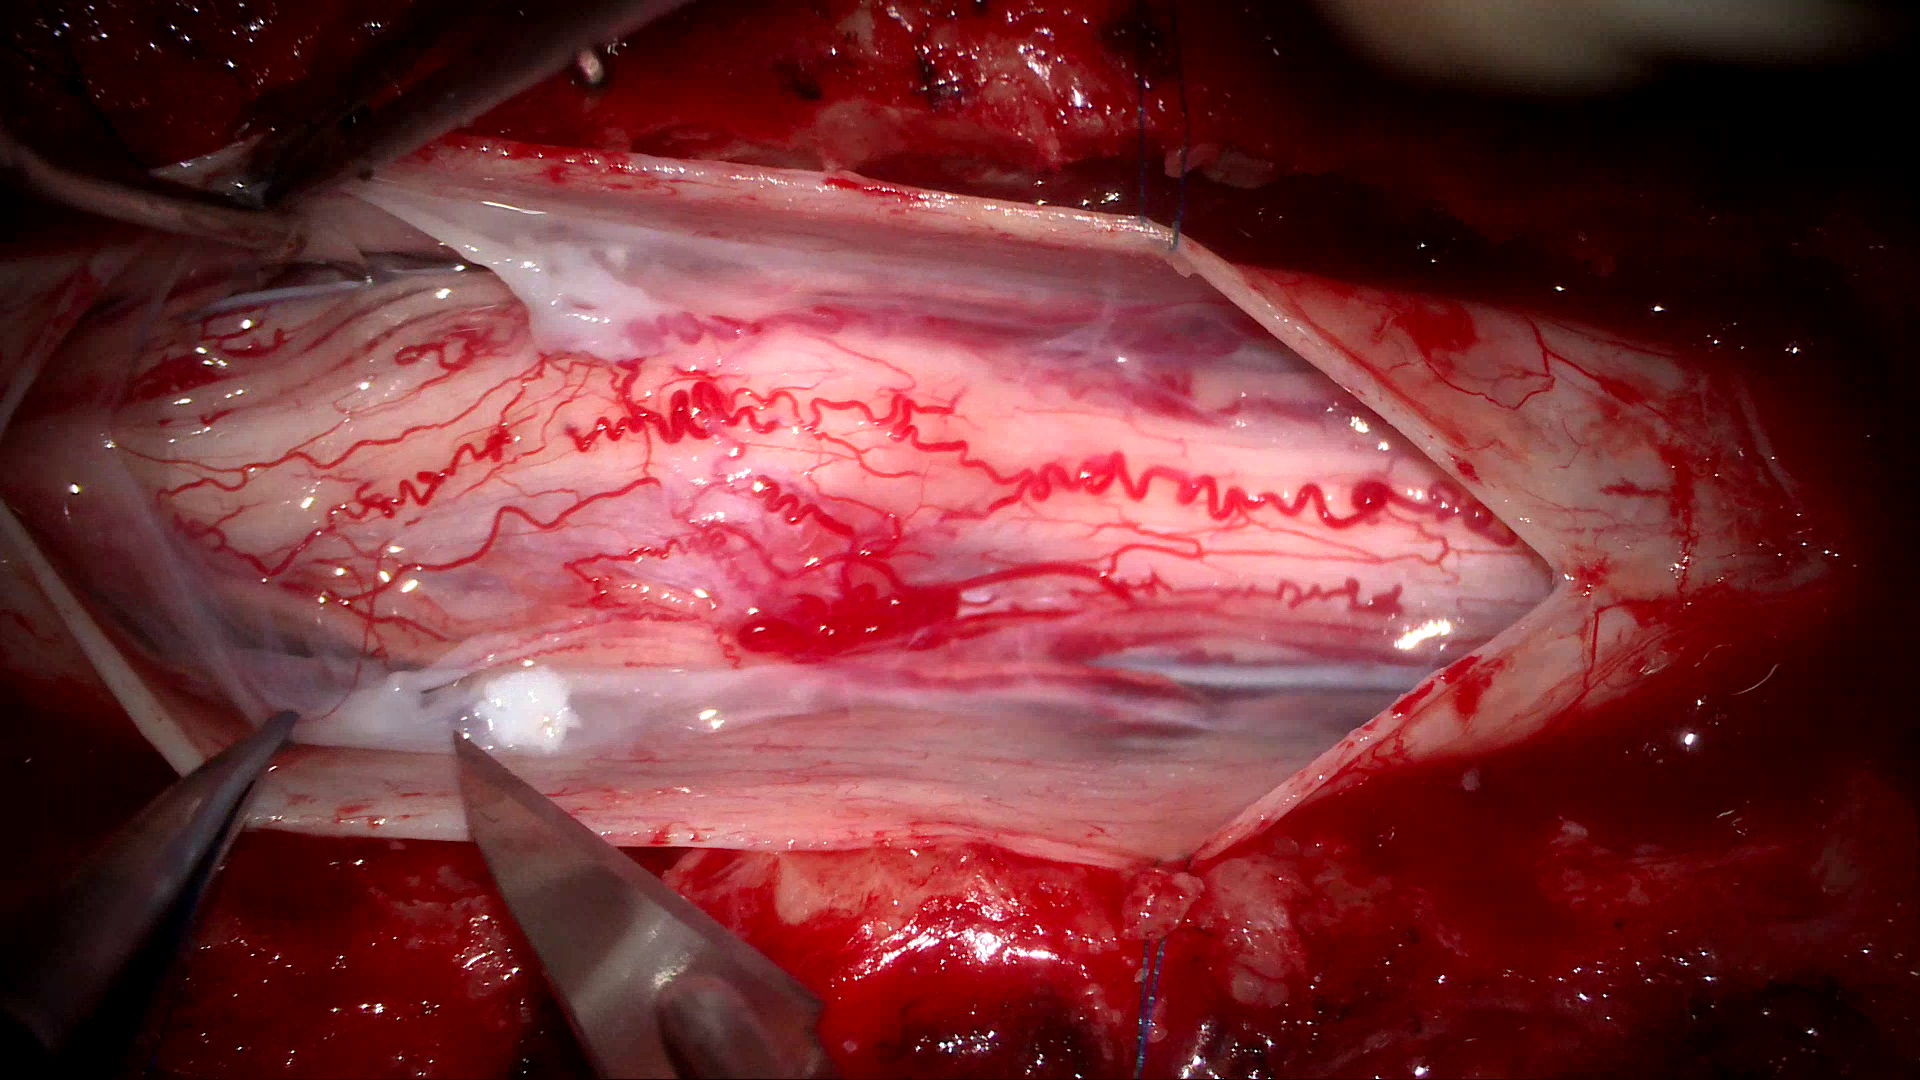

Echipa chirurgicală a fost nevoită să utilizeze o tehnică specială de abord, o mielotomie laterală

Dată fiind poziția excentrică a tumorii, echipa chirurgicală a fost nevoită să utilizeze o tehnică specială de abord, o mielotomie laterală, care a permis disecția circumferențială și îndepărtarea completă a formațiunii tumorale, fără lezarea țesutului medular. Tumora a fost excizată integral, într-o singură piesă.

Tumora a fost excizată integral, într-o singură piesă